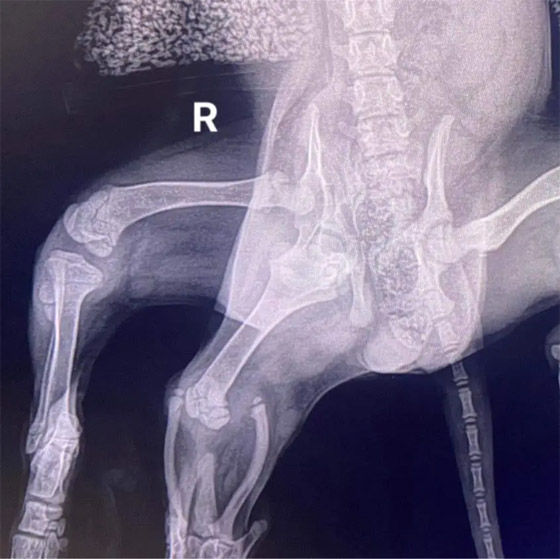

نجح الأطباء بإزالة طرفين زائدين لكلبة من نوع "سبنيلي" ولدت بـ6 قوائم، عثر عليها في مرآب متجر بقالة وسط بيمبروك في ويلز بالمملكة المتحدة. وأطلق على الكلبة اسم "آرييل"، وهو اسم شخصية فيلم "ليتل ميرميد" لأن العضوين الزائدين يبدوان مثل زعنفة، حيث ولدت بعدة عيوب خلقية.

وأخذها ملجأ "غريناكريس" للإنقاذ، وجمع الأموال لإجراء الجراحة. وقالت فيكي بلاك، مديرة مستشفى لانغفورد البيطري "إنها بحال رائعة"، مشيرا إلى أن المستشفى لم ير من قبل كلبا بست أرجل، كما لم تجر مثل هذه العملية الجراحية من قبل. وأوضحت بلاك: "كانت آرييل كلبة صغيرة بحال معقدة"، لم يبد أن الساقين الإضافيتين لهما نفع أو أهمية، وكانتا تتدليان جوار ذيلها، وكانت تمشي بشكل مرتبك. وأمس السبت، سمح بخروجها إلى العشب أمام المستشفى، وكانت تتمتع بنشاط وتركض بسعادة.